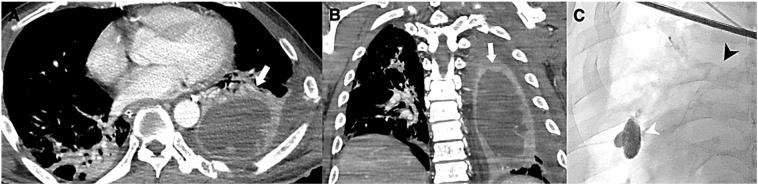

Traumatic pulmonary giant hematoma, resulting from blunt trauma, is a relatively rare event. Here, we report the rare case of a patient with a giant traumatic pulmonary hematoma that was associated with blunt trauma. A 50-year-old man was admitted to our medical center after a fall from a height of 5 m. He was diagnosed with pulmonary contusion, and tests showed a huge pulmonary hematoma of approximately 8.2 × 5.3 × 13.2 cm in the left lung field along with other significant injuries. Treatment comprised of aggressive coagulation management, broad-spectrum antibiotics, and pulmonary hygiene. The patient's symptoms gradually improved and magnetic resonance scan revealed that he did not develop an abscess formation. No complications were seen at the 6 months follow-up visit. If the above mentioned measures would have failed to control the bleeding or secondary infection, then emergency surgery would have been warranted. Awareness of this kind of injury and efforts to reduce infection are important to guide the giant traumatic pulmonary hematoma to the benign course.

创伤性肺巨大血肿由钝性创伤引起,是一种相对罕见的情况。在此,我们报告一例与钝性创伤相关的创伤性肺巨大血肿的罕见病例。一名50岁男性从5米高处坠落后来到我们的医疗中心。他被诊断为肺挫伤,检查显示左肺野有一个巨大的肺血肿,大小约为8.2×5.3×13.2厘米,同时伴有其他严重损伤。治疗包括积极的凝血管理、广谱抗生素和肺部护理。患者的症状逐渐改善,磁共振扫描显示他没有形成脓肿。在6个月的随访中未发现并发症。如果上述措施未能控制出血或继发感染,则有必要进行急诊手术。认识到这种损伤并努力减少感染对于引导创伤性肺巨大血肿走向良性病程很重要。